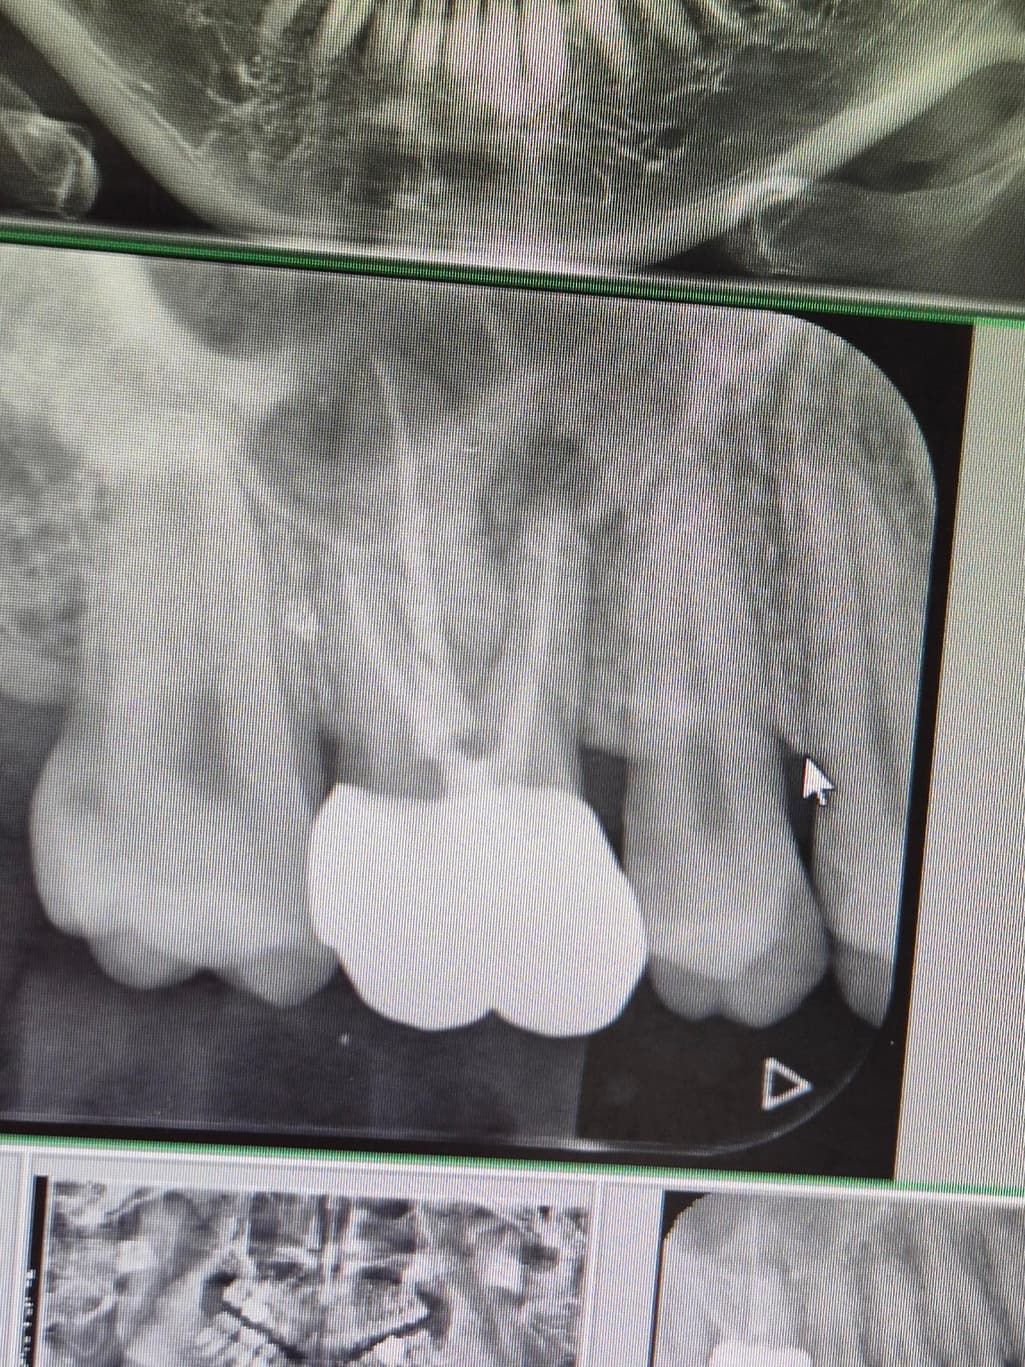

요 상태로 지금 2~3년 지났습니다 통증은 없고 잇몸 뿌리염증이 커지지 않으며 고름 주머니도 없는 상태입니다 재신경치료나 다른 치료를 하지 않아도 되나요?

신경치료는 크게 문제는 없어보입니다. 정말 염증이 더 커지는 게 아니면 지켜볼 수도 있습니다.

신경치료를 하고나서 뿌리끝에 염증이 잇어도 활성화되지 않고 증상이 없다면 그냥 사용하셔도 크게 문제가 되진 않습니다.

신경치료를 하고 치아뿌리에 염증이 생겼다는 것은 치아 내부의 신경관에 감염이 되었다는 것입니다. 이런 경우 제 신경 치료가 필요할 수 있습니다. 염증 부위가 커지거나 한다면 치아를 유지하는 것이 힘들 수 있으니 주기적으로 치아 뿌리 끝에 염증의 크기를 확인해주는 것이 좋습니다.

이미 신경치료가 되어있고 보기에 퀄리티도 괜찮아보입니다 그래서 저 염증이 커지진 않는지 정기적으로 검사하면서 지켜보는 것도 방법입니다

아마도 신경관하나(mb2) 놓친게 있어서 거기서 비롯된 염증일거라 추정됩니다